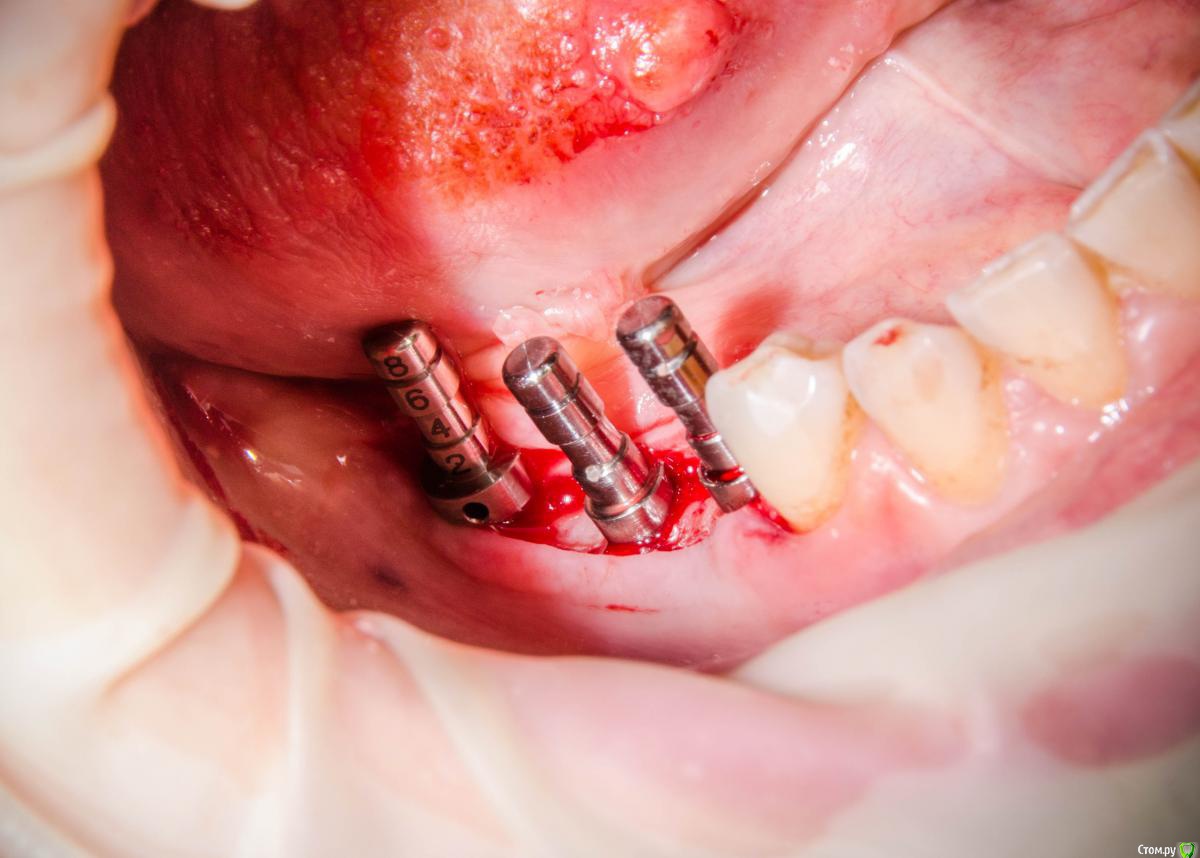

kamranchick Опубликовано 8 февраля, 2017 Автор Поделиться Опубликовано 8 февраля, 2017 А что и какой размер ставили?Послабляющий распил не делали?я тут не делал распилы, тут нет расщепления3,5-8,5 Ссылка на комментарий

kamranchick Опубликовано 8 февраля, 2017 Автор Поделиться Опубликовано 8 февраля, 2017 Спасибо за публикацию.Какова ширина гребня?5мм сверху в области кристального модуля имплантата дальше около 7мм) Ссылка на комментарий